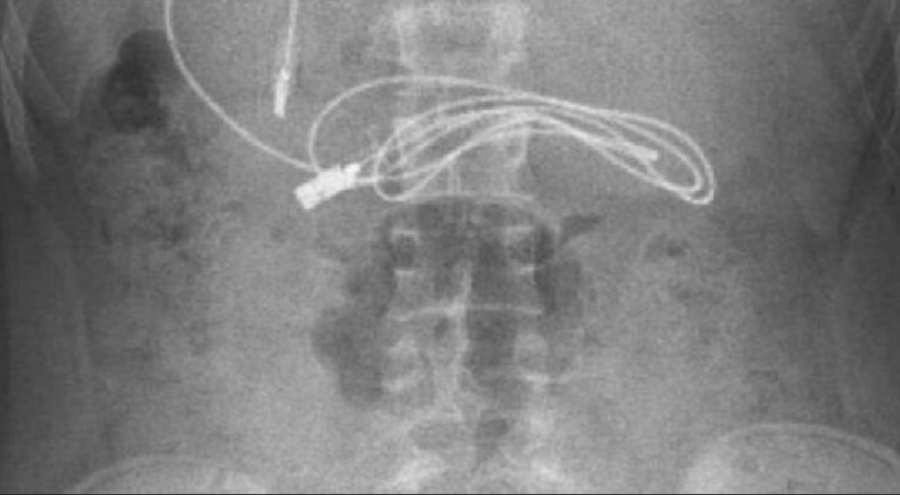

Diyarbakır'da kusma ve bulantı şikayetiyle hastaneye götürülen, çekilen röntgeninde 1 metrelik şarj kablosu ve toka yuttuğu tespit edilen 15 yaşındaki erkek çocuğu, Elazığ'da gerçekleştirilen operasyonla yuttuğu cisimlerden kurtuldu.

Diyarbakır'da kusma ve bulantı şikayetiyle ailesi tarafından hastaneye götürülen erkek çocuğunun çekilen röntgeninde, midesinde şarj kablosu ve toka olduğu tespit edildi. Bunun üzerine çocuk, ambulans ile Fırat Üniversitesi Hastanesi'ne sevk edildi.

Ameliyatı gerçekleştiren Prof. Dr. Yaşar Doğan, kablonun bir ucunun ince bağırsağa geçmesi nedeniyle zorlandıklarını ifade ederek, "Hastanın kusma ve karın ağrısı şikayetleri olması üzerine sağlık kuruluşuna başvurulmuş. Orada yapılan incelemelerde hastanın midesinde kablo tespit edilmesi üzerine bize danışıldı.

112 aracılığıyla hastaya gerekli işlemi yapıp yapmayacaklarını bize sordular. Biz de hastayı bize gönderebileceklerini kendilerine ilettik. Hasta bize geldikten sonra ön hazırlık yapıldı ve gerekli olan açlık süresinin ardından hastaya endoskopik işlem yapıldı.

Endoskopik işlemle midedeki kablo çıkarıldı. Kabloyu çıkarırken açıkçası zorlandık, çünkü kablonun bir ucu ince bağırsağa geçmişti. İşlem başarılı bir şekilde sonlandırıldıktan sonra hasta sağlıklı bir şekilde evine gönderildi" dedi.